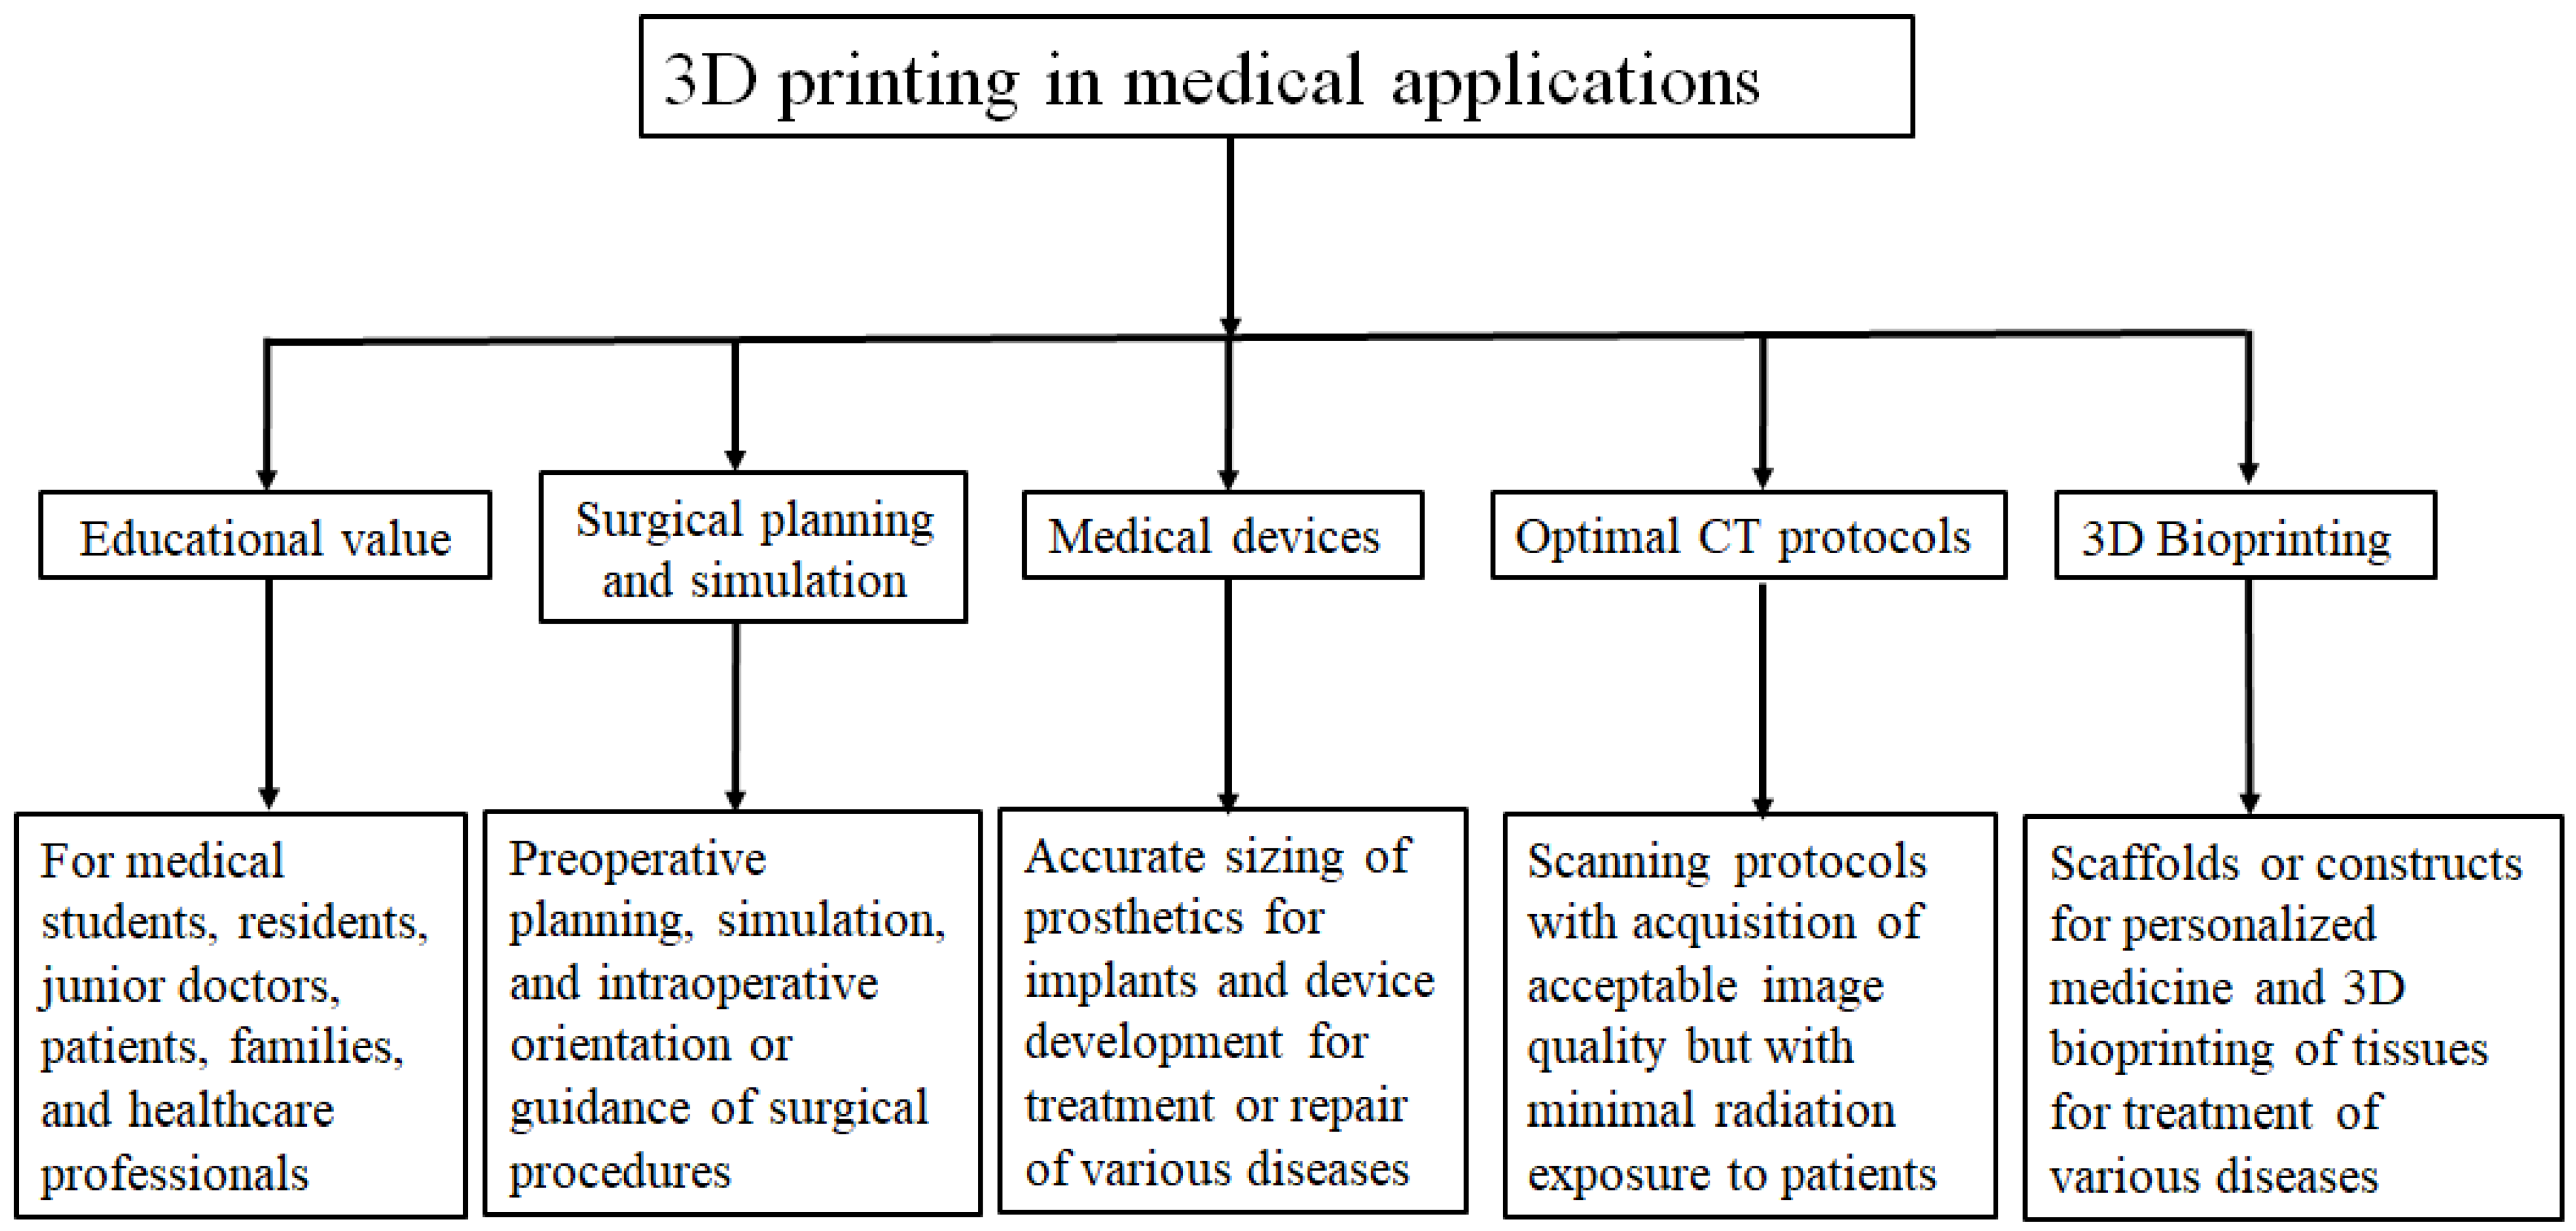

:1. Introduction

2. 3D Printing Preparation: Image Post-Processing and Segmentation

4. Usefulness of 3D-Printed Models in Cardiovascular Disease